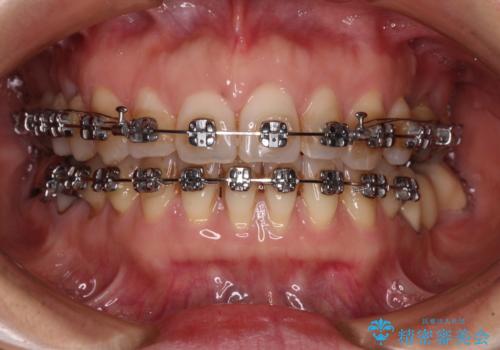

正中のズレと飛び出した前歯を改善 メタルブラケットでの抜歯矯正

- 飛び出した上顎前歯と正中のズレを気にして来院された患者様です。

上顎正中が右側にずれていたので、むし歯が酷く抜歯が必要な左側臼歯を抜歯して正中を改善することとしました。

左下には新しいセラミックのブリッジが装着されていたため、ブリッジを壊さずに改善できるところまで咬み合わせを改善していくこととしました。

右上小臼歯は銀歯が装着されており、ワイヤー矯正の装置が装着できないため、事前に仮歯に変えてから矯正治療を行い、その後オールセラミッククラウンにて補綴治療を行いました。